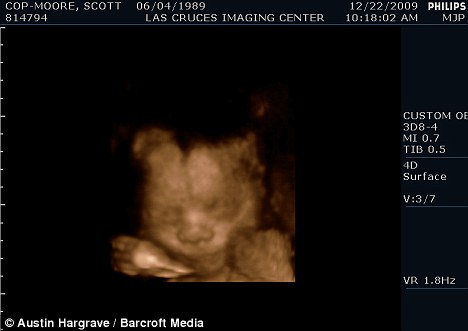

掃描顯示斯科特懷的是個男孩

現年30歲的斯科特·穆爾和丈夫托馬斯來自美國加利福尼亞州,兩人原先都是女性,托馬斯接受過變性手術后成為真正的男子漢,斯科特仍然留有一些女性器官并持有女性出生證明,所以他們的婚姻是合法的。目前他們已經知道未出生的孩子是個男孩,準備給他取名“邁爾斯”。

2009年6月,斯科特從一名男性朋友那里取得精子,并通過人工受精成功懷孕。他打算在當地的醫院自然分娩。